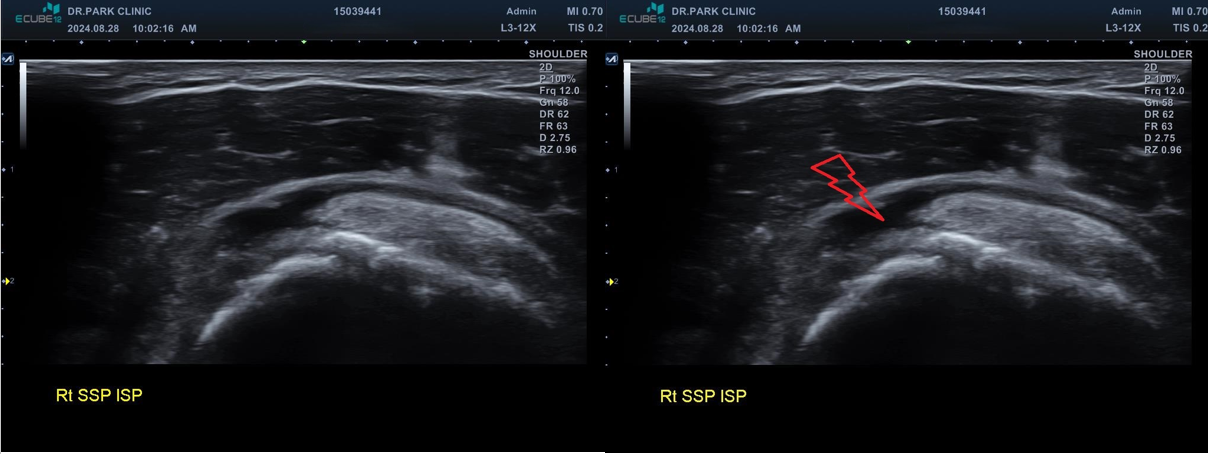

진짜 문제는 초음파 검사였는데요... 초음파 검사상에는....

마지막 초음파에서는 어깨 극상근의 파열 소견이 관찰되고 있습니다. 정확한건 mri 를 찍어봐야 하겠지만 찢어진 길이와 정도로 봐서는 수술이 필요한 극상근 전층파열로 생각이 됩니다.